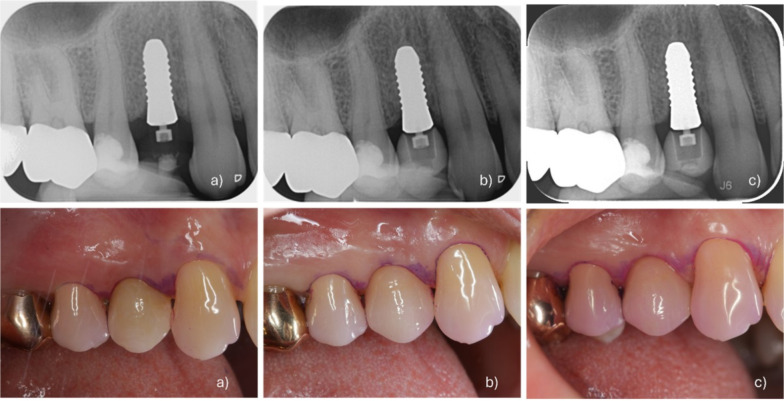

Methods: Twenty-four patients received single two-piece zirconia implants (CERALOG® Hexalobe) in healed sites. After a 6-month healing period, implants received provisional screw-retained crowns on PEKK temporary abutments, followed by definitive lithium disilicate crowns (IPS e.max Press) on PEKK abutments. Clinical and radiographic examinations were performed at implant placement, re-entry, definitive loading, and 12-month follow-up, along with patient-reported outcome measures.

Results: The implant survival rate at 12 months was 60.9%. Nine implants were lost: two due to lack of osseointegration at re-entry, four due to mobility after loading, and three due to fractures in the coronal third after loading. Surviving implants showed stable soft tissue parameters with mean probing pocket depths of 2.7 ± 0.7 mm at 12 months. The mean distance from implant shoulder to first bone contact decreased from 1.9 ± 0.6 mm at loading to 1.4 ± 0.6 mm at 12 months. Patients with surviving implants reported high satisfaction scores (4.8 ± 0.4) for function and aesthetics.